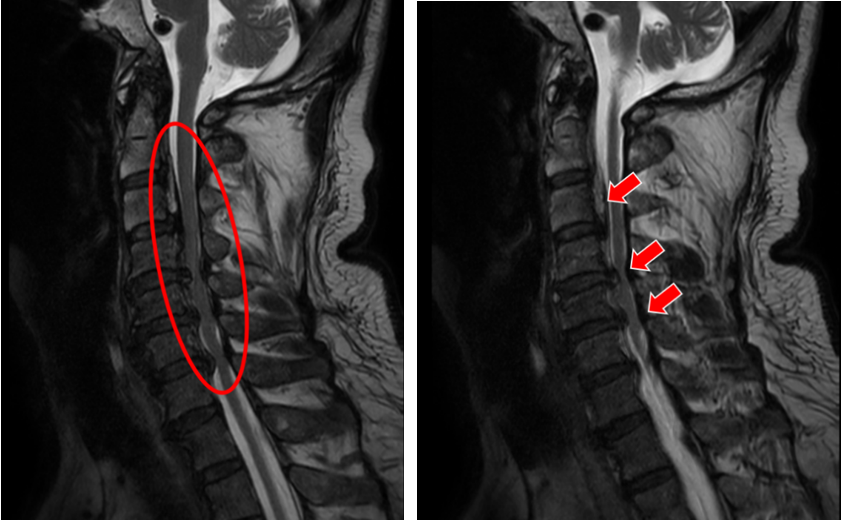

(姐姐的颈椎CT显示她的颈椎椎体同样存在明显的后纵韧带骨化,与弟弟不同的是,她的韧带骨化程度更严重)

(颈椎MRI提示C2-6椎管狭窄,脊髓受压严重)